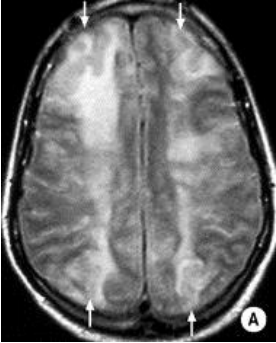

Case 3 Q# 1 of 4

• 61 year old man

• Presents with right arm and leg numbness and weakness and slurred speech.

• Symptoms lasted about 20 minutes and resolved

• PMHx: type I diabetes, hypertension, and hyperlipidemia

• Exam on presentation is normal. MRI is attached.

What is the etiology of his stroke / TIA?

Microemboli; specifically, from his thrombosed left internal coronary artery.

How is the etiology of his stroke consistent with the MRI?

The MRI shows very tiny, punctate infarcts throughout several axial layers of the cortex that all appear to be in the same location sagitally/coronally, aka all in the territory of one small vessel! This supports a small embolus that occluded only the area of one small brain vessel.

What about the MRI helps you rule out a lacunar infarct? What pathogenesis is typically responsible for lacunar infarct?

Lacunar infarcts tend to affect only deeper structures of the brain, and tend to measure 1-1.5cm (somewhat larger than this tiny punctate infarction).

Hyaline arteriolosclerosis typically precipitates lacunar strokes.

What is the etiology of the MRI image below?

Cardioembolism

• When you see multiple small infarcts like this, think of a shower of emboli dispersed throughout ALL territories of the brain. A cardioembolism is more likely to cause this than say, a carotid artery embolism.

• Cardioembolisms tend to cause larger strokes rather than TIAs - typically a worse prognosis.